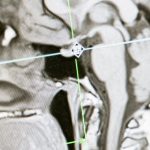

Les manipulations vertébrales sont une composante clé de la médecine manuelle. Ces techniques visent à réaligner les vertèbres déplacées et à soustraire la pression exercée sur les nerfs. En agissant directement sur les articulations de la colonne vertébrale, ces manipulations favorisent une récupération rapide et aident à soulager la douleur lombaire.

Les praticiens de la médecine manuelle sont formés pour évaluer et traiter les dysfonctionnements du corps. Grâce à une investigation minutieuse des antécédents médicaux des patients et une analyse physique complète, ils peuvent identifier les causes sous-jacentes des douleurs lombaires. Leurs interventions comprennent des techniques spécifiques qui visent à relâcher les tensions accumulées, à améliorer la circulation sanguine et à restaurer un équilibre musculo-squelettique. Par exemple, les manipulations vertébrales permettent de réaligner les vertèbres, réduisant ainsi la pression sur les nerfs et soulageant la douleur.